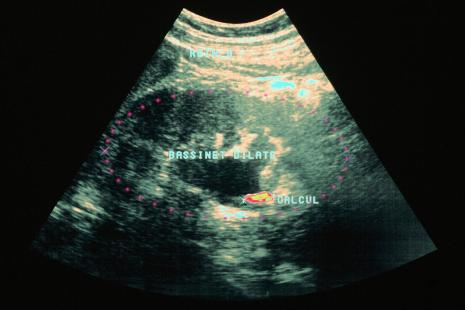

La troisième anomalie correspond à la dilatation des cavités pyélocalicielles, assez fréquente. À l’imagerie, les cavités excrétrices, normalement virtuelles, apparaissent dilatées en cas de rétention d’urine dans le rein voire dans l’uretère, traduisant la présence d’un obstacle à l’écoulement urinaire. « La dilatation des cavités pyélocalicielles peut résulter de nombreuses pathologies, certaines graves, et ne doit pas être négligée », avertit le Pr Bigot. L’échographie permet de faire le tri entre une dilatation du rein seul ou de l’uretère associé. S’il apparaît dilaté depuis sa portion proximale jusqu’à son abouchement vésical, plusieurs diagnostics sont possibles : anomalie de l’insertion vésicale avec sténose, tumeur vésicale, pelvienne ou prostatique envahissant l’orifice urétéral. Le bilan doit comporter la recherche d’une hématurie, un toucher rectal et/ou vaginal selon le cas, un dosage du PSA, ainsi qu’une fibroscopie vésicale. Une dilatation urétérale peut également s’observer en cas de reflux vésico-urétéral (méat urétéral refluent, globe vésical dû à une rétention chronique d’urine secondaire, par exemple, à une hypertrophie prostatique). Lorsqu’un obstacle se situe au milieu de l’uretère (calcul ou tumeur), on observe une dilatation des voies excrétrices uniquement en amont de l’obstacle. Autre cause possible : un syndrome de la jonction pyélo-urétérale (rétrécissement de la jonction entre le bassinet et l’uretère), la malformation rénale la plus fréquente.

« Certaines situations relèvent de l’urgence absolue, prévient l’urologue. Lorsqu’un patient présente une fièvre - même une fébricule - avec un syndrome inflammatoire et une dilatation des voies excrétrices rénales, la présence de bactéries sous pression expose à un risque élevé de septicémie avec décompensation brutale et pronostic vital engagé. Le patient, même s’il peut sembler cliniquement stable, doit être adressé immédiatement aux urgences. »

En l’absence de fièvre ou de syndrome inflammatoire, si la symptomatologie se limite à une colique néphrétique ou à une pesanteur lombaire, tout en orientant vers l’urologue, il est recommandé d’administrer, en plus du paracétamol, un anti-inflammatoire non stéroïdien.

La quatrième anomalie concerne les calculs rénaux. Si le rein est dilaté avec présence de fièvre, il s’agit d’une urgence. Sans fièvre, mais avec un calcul visible, un uroscanner en semi-urgence et une consultation en urologie s’imposent. « Il faut alors informer le patient d’une possible colique néphrétique, commente Pierre Bigot, lui prescrire paracétamol/AINS en cas de crise et lui conseiller de consulter en urgence dès l’apparition d’une douleur s’accompagnant de fièvre. »